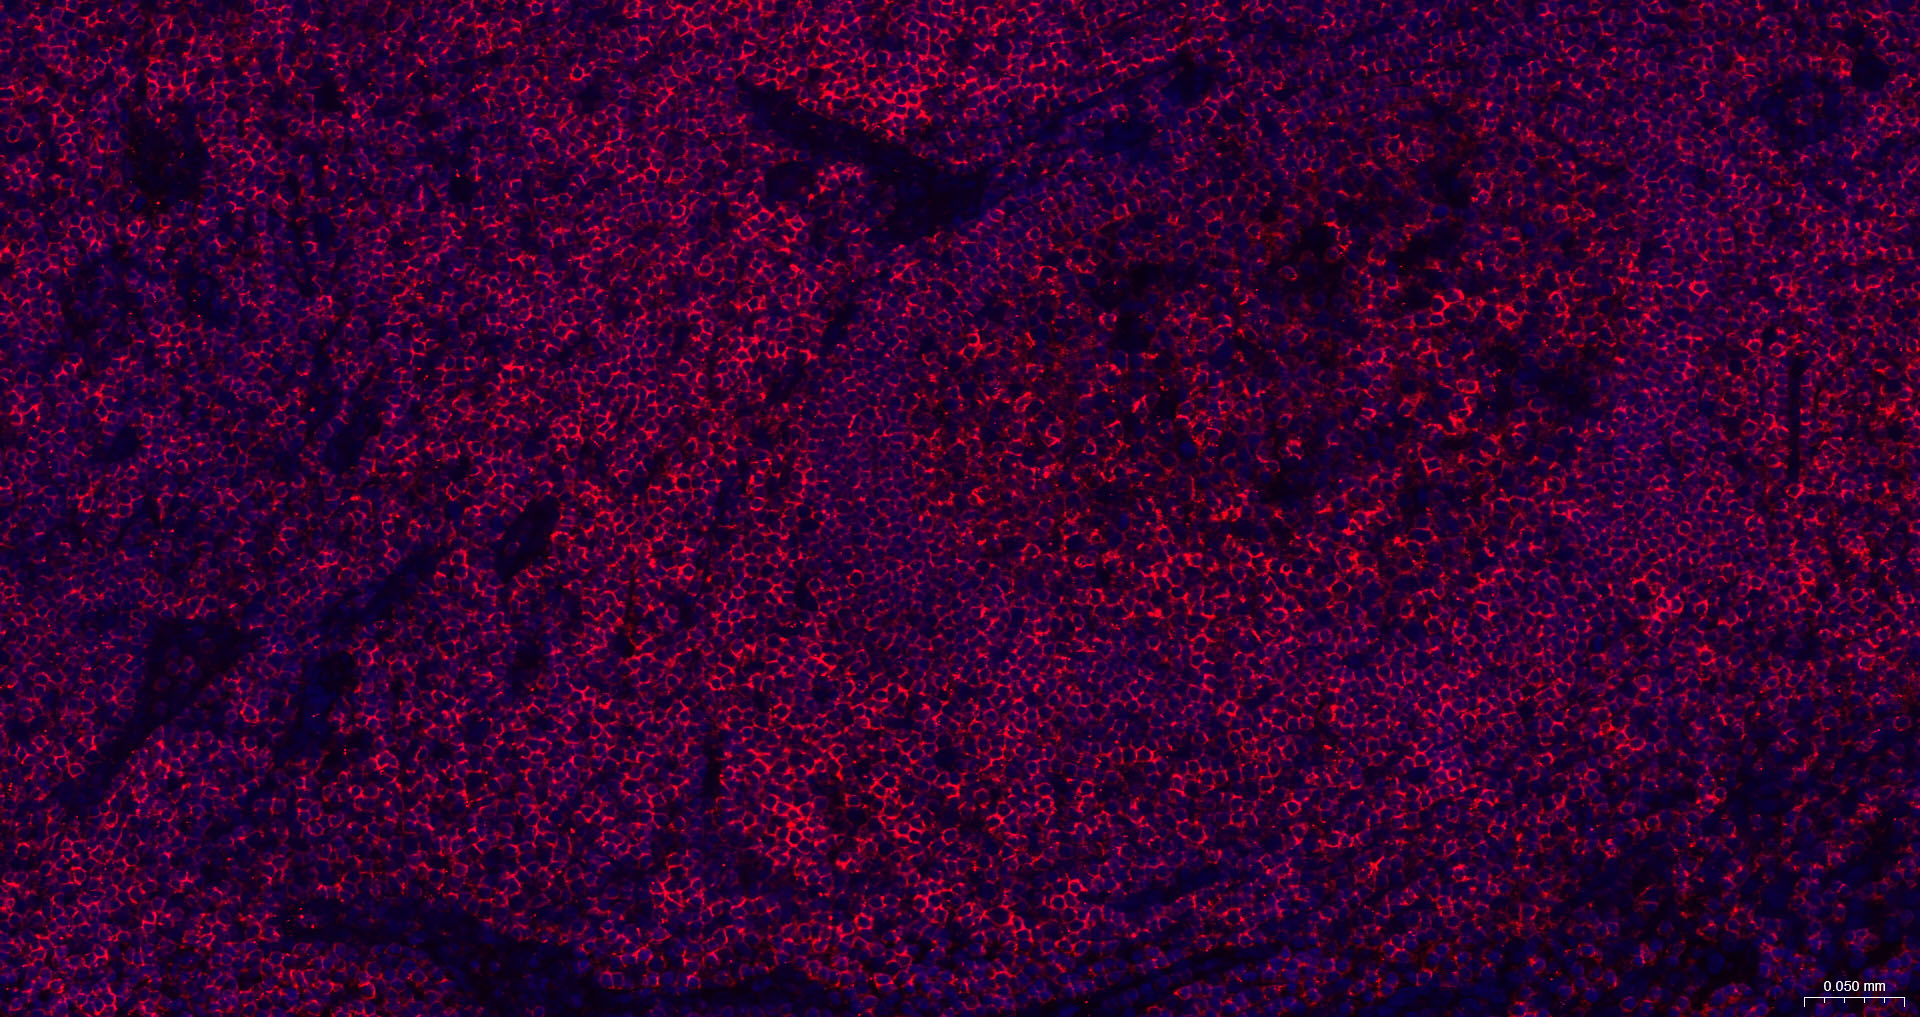

CD45 Recombinant Antibody

• IHC-F

• IF(IHC-P)

IHC-F IHC-F1:100-500

IF(IHC-P) IFIHC-P1:100-500